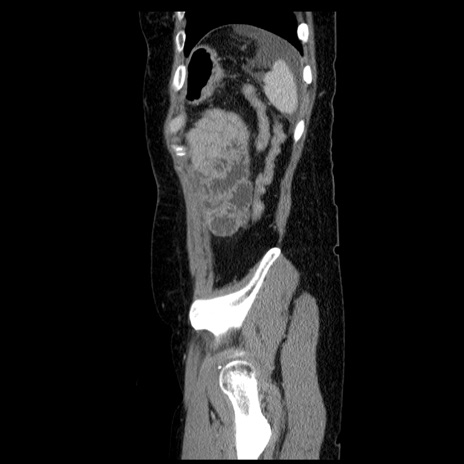

横断像